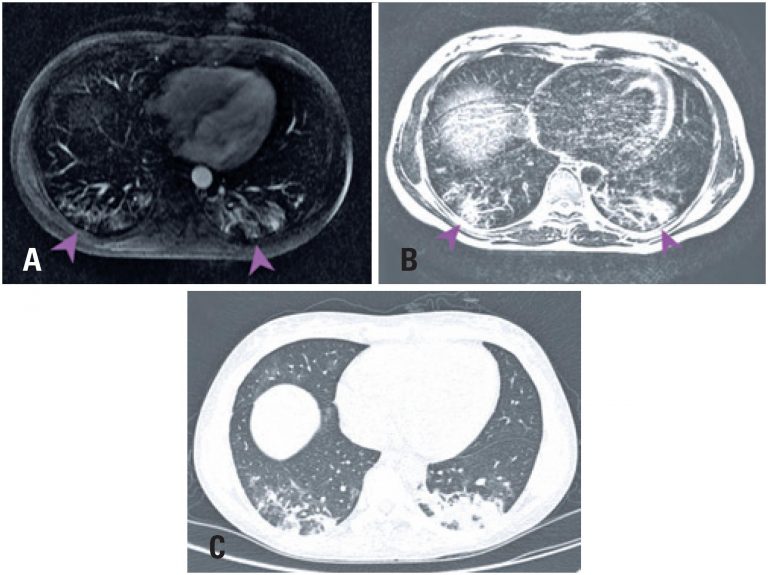

Paciente do sexo feminino, 34 anos, com antecedente pessoal de retocolite ulcerativa há 5 anos, em uso de sulfassalazina e mesalazina, deu entrada no pronto-socorro apresentando quadro de astenia, dispneia, febre e tosse associada a escarro hemoptoico há 8 dias, saturando 97% ao ar ambiente. Realizou tomografia computadorizada (TC) () que demonstrou opacidade em vidro fosco esparsa, embora mais evidente no contorno posterior dos lobos inferiores. Foi admitida para internação e teve o diagnóstico de infecção pelo novo coronavírus por meio de reação em cadeia da polimerase com transcrição reversa (rt-PCR). Durante a internação, apresentou dor abdominal difusa com fezes líquidas, escurecidas e de odor forte, realizando ressonância magnética (RM) do abdome superior para avaliação.

Os cortes da RM () evidenciaram opacidades bilaterais nas bases pulmonares, com predomínio posterior e subpleural, com aspecto similar àquele demonstrado na TC.